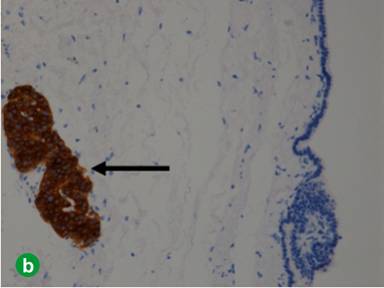

The cystic lining cells were focally reactive to CK7 and Trypsin (Figure 6a) but negative for calretinin, WT1, PAX8, CD31, and CK20. The luminal border of the epithelium was also reactive to EMA. Histochemical staining for PAS was negative in the epithelium. The residual pancreatic islet could be highlighted by IHC stain for synaptophysin (Figure 6b). The whole picture was more like a rare acinar cell cystadenoma.

|

Figure 6. a. The lining cells were reactive to Trypsin. b. The residual islets of Langerhans (arrow) were positive for synaptophysin, but the lining epithelium was negative. |